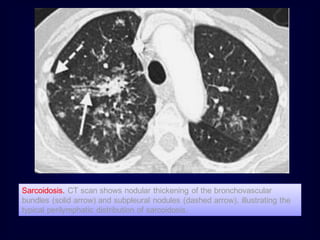

Sarcoidosis. CT scan shows nodular thickening of the bronchovascular

bundles (solid arrow) and subpleural nodules (dashed arrow), illustrating the

typical perilymphatic distribution of sarcoidosis.